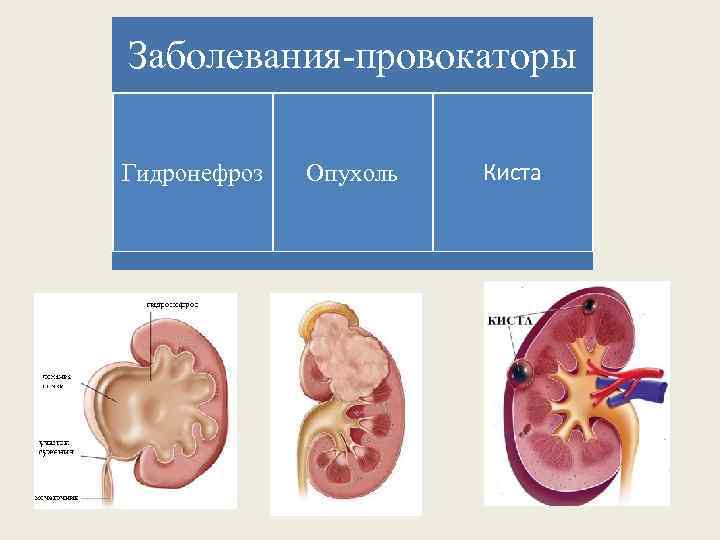

Заболевания-провокаторы Гидронефроз Опухоль Киста